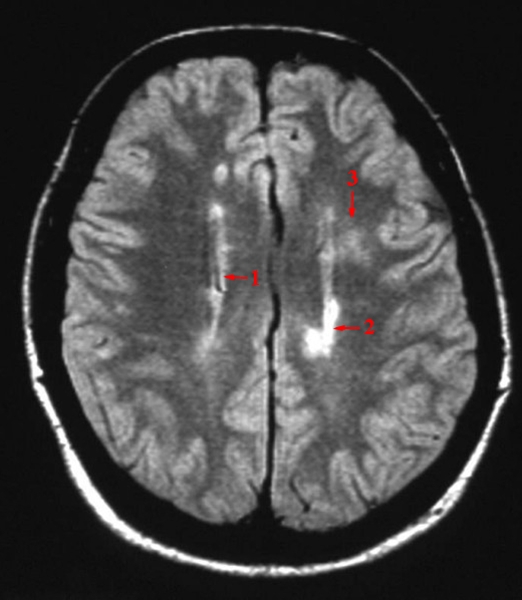

MR - tværsnit. Intenst hvide områder repræsenterer demyelinisering